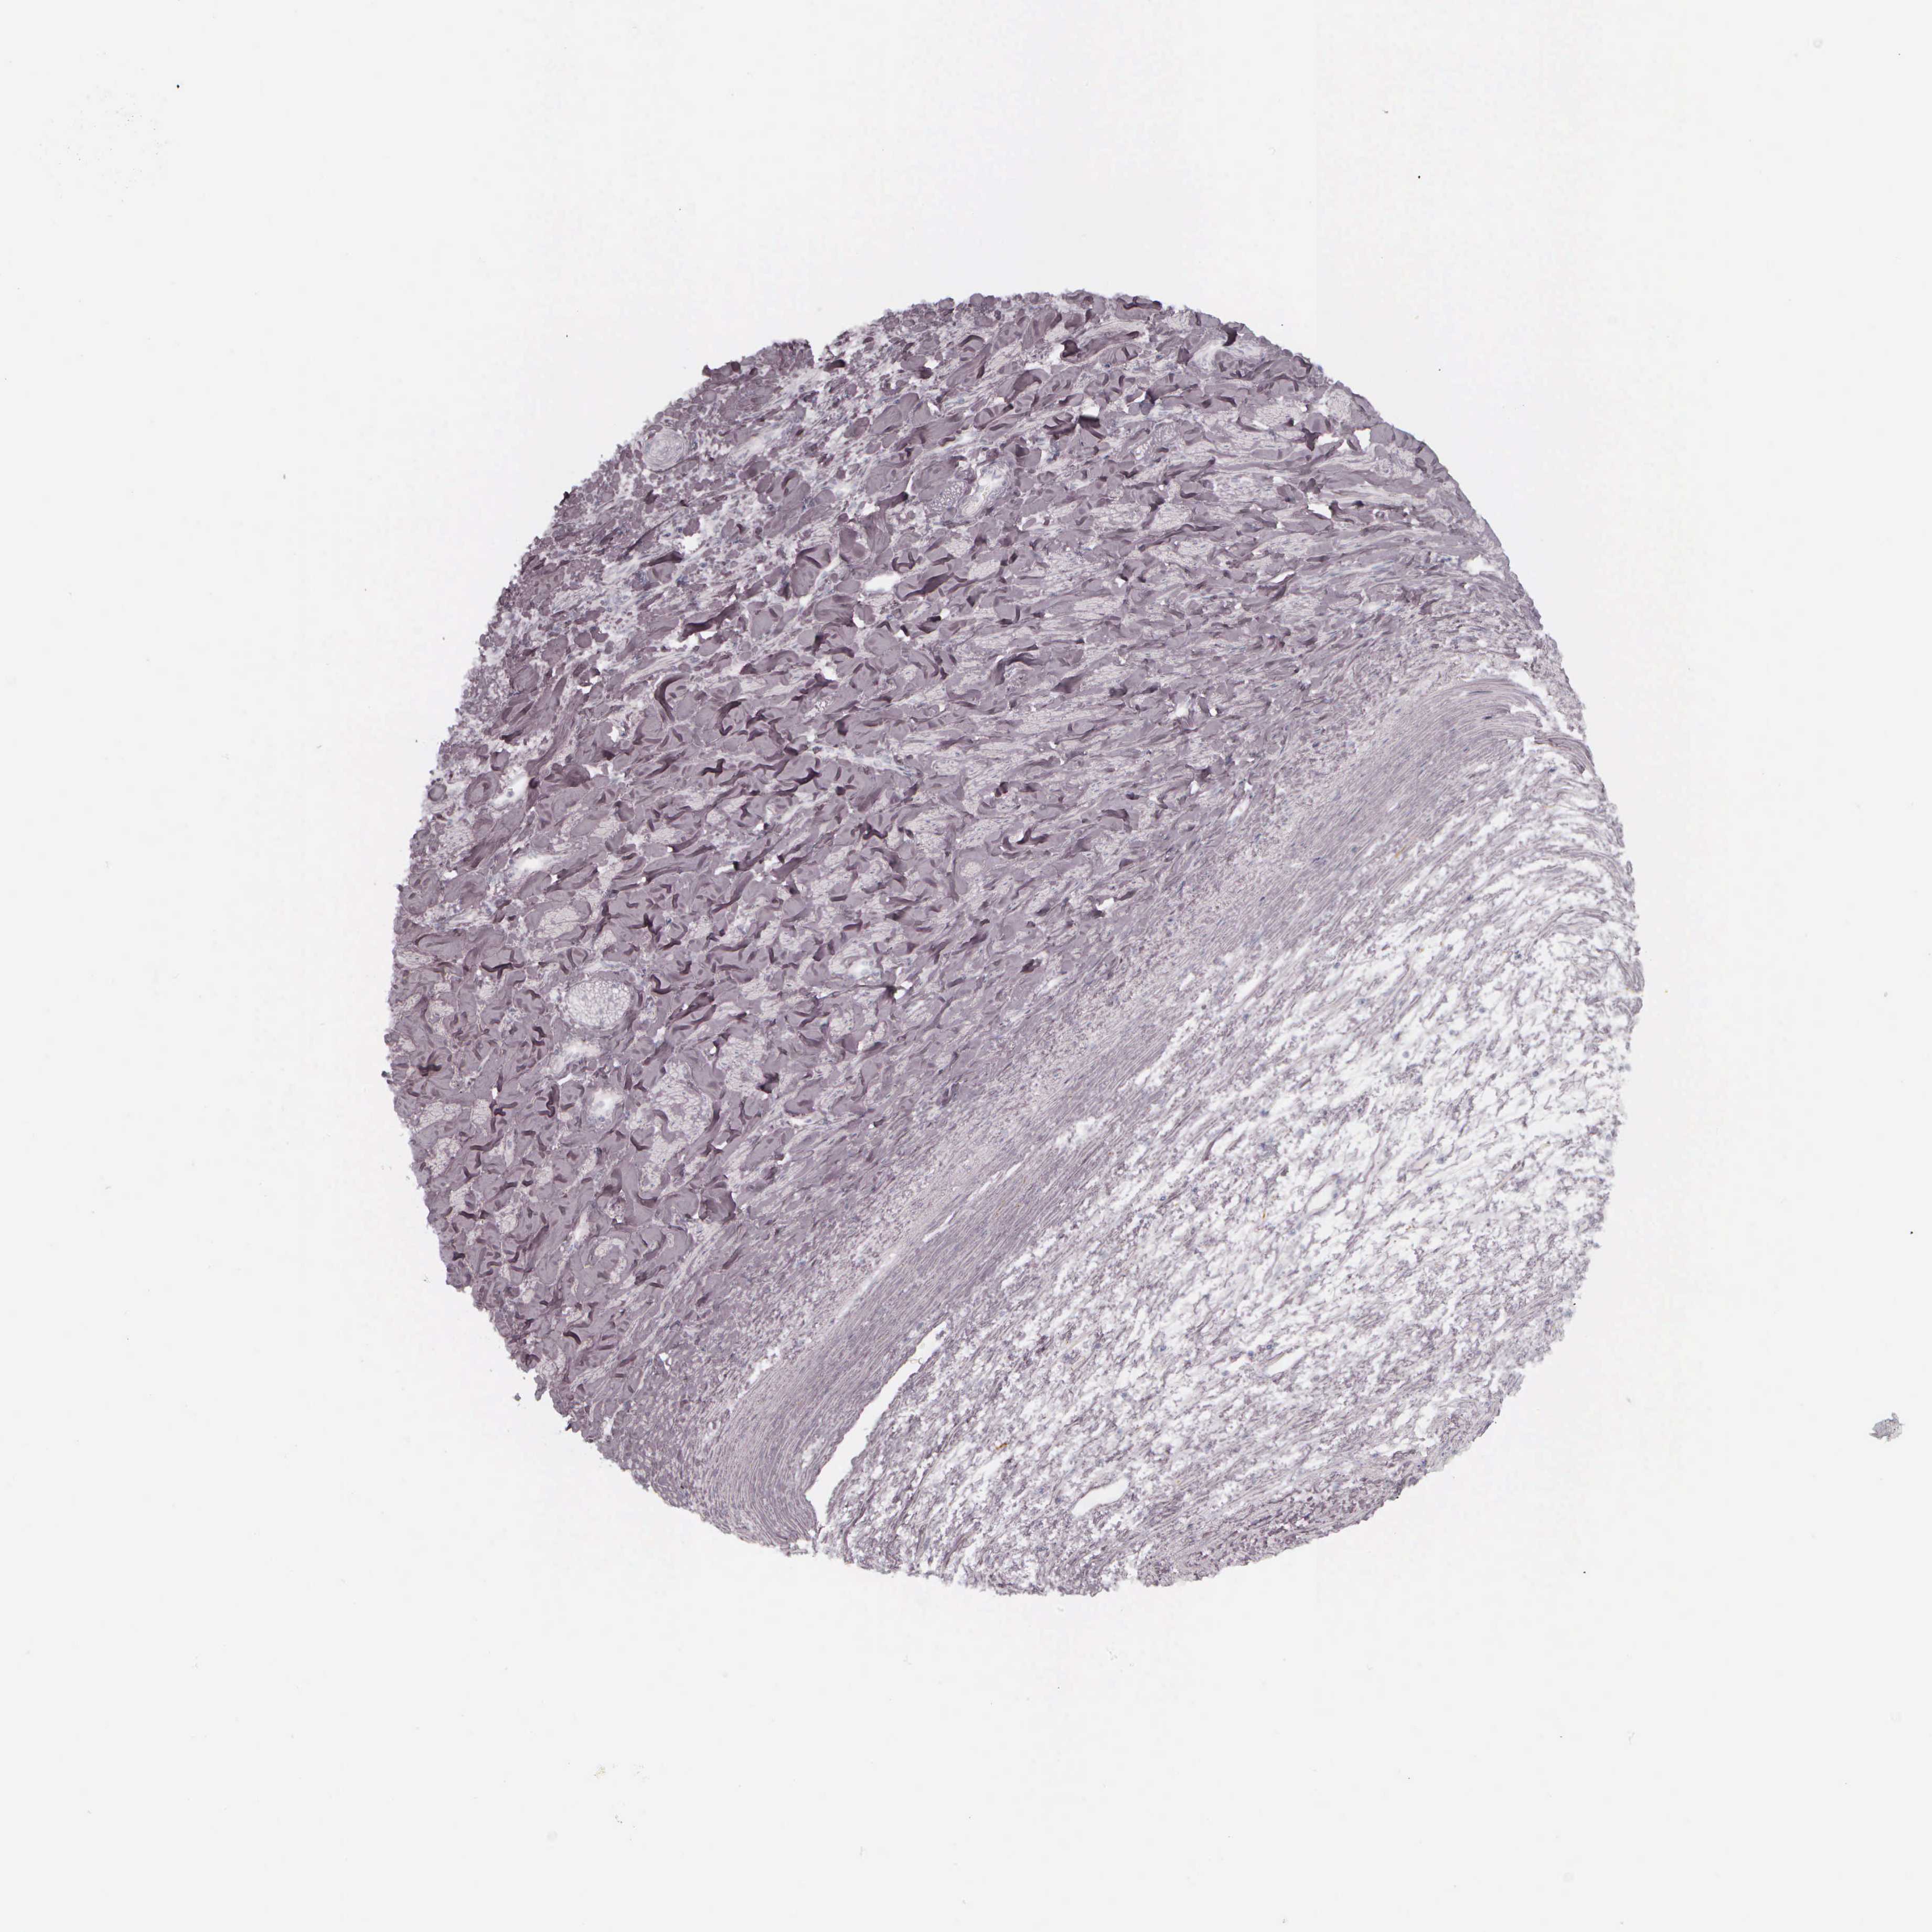

LIVER CANCER - Protein expressioni

A mouse-over function shows sample information and annotation data. Click on an image to view it in a full screen mode. Samples can be filtered based on level of antibody staining by selecting one or several of the following categories: high, medium, low and not detected. The assay and annotation is described here.

Note that samples used for immunohistochemistry by the Human Protein Atlas do not correspond to samples in the TCGA dataset.

Antibody HPA000452

Antibody HPA023040

Antibody CAB000134

Staining

High

Medium

Low

Not detected

Intensity

Strong

Moderate

Weak

Negative

Quantity

>75%

75%-25%

<25%

None

Location

Nuclear

Cytoplasmic/membranous

Cytoplasmic/membranous,nuclear

Carcinoma, Hepatocellular, NOS

Cholangiocarcinoma